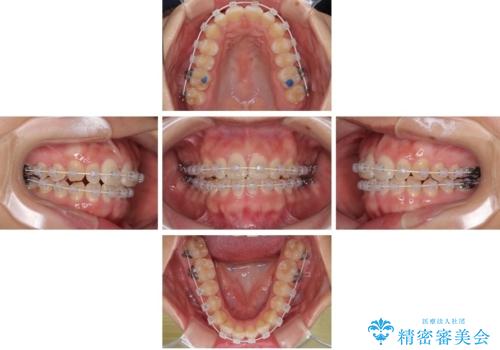

目立ちにくい表側装置で1年完了!狭いアーチを側方拡大し前歯のデコボコを整えた症例

- 前歯のデコボコが気になるでのことで来院された患者様です。

歯列アーチが狭くスペース不足により前歯がデコボコしている状態でした。見た目を改善しつつ、前歯を前方に突出させず、自然な笑顔を目指したいというご希望でした。

治療計画

・アーチを側方に拡大して歯が並ぶスペースを確保

・抜歯は避け、非抜歯での対応

・目立ちにくい審美装置による矯正

・治療期間をできるだけ短縮するために、綿密な装置管理と協力体制を構築